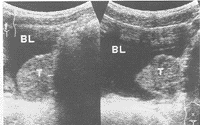

患者男,8岁。因阵发性头痛2周,小便时加重并伴大汗淋漓5 d来我院就诊。查体:血压180/120 mm Hg(1 mm Hg=0.133 kPa),心肺正常,其他未见异常。B超检查显示:膀胱左侧壁近颈部见一 3.0 cm×3.5 cm的实质性团块,突入膀胱腔内,不随体位变化而移动,表面较光滑,边界清,内部回声较均匀(图1)。彩色多普勒血流显像显示:团块内血流信号较丰富。超声提示:膀胱肿瘤,膀胱内异位嗜铬细胞瘤不能除外。经手术切除肿瘤,病理诊断为膀胱内异位嗜铬细胞瘤。

膀胱左侧壁近颈部 3.0 cm×3.5 cm的实性团块,突入膀胱腔内,表面光滑,边界清,内部回声较均匀

图1 膀胱异位嗜铬细胞瘤声像图, 百拇医药